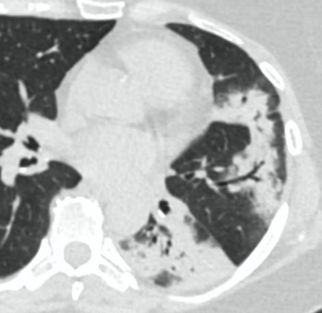

4.3. ЛУЧЕВАЯ ДИАГНОСТИКА COVID-19

Методы лучевой диагностики применяют для выявления COVID-19 пневмоний, их осложнений, дифференциальной диагностики с другими заболеваниями легких, а также для определения степени выраженности и динамики изменений, оценки эффективности проводимой терапии.

К методам лучевой диагностики патологии ОГК пациентов с предполагаемой/установленной COVID-19 пневмонией относят:

- Компьютерную томографию легких (КТ),

КТ имеет высокую чувствительность в выявлении изменений в легких, характерных для COVID-19. Применение КТ целесообразно для первичной оценки состояния ОГК у пациентов с тяжелыми прогрессирующими формами заболевания, а также для дифференциальной диагностики выявленных изменений и оценки динамики процесса. КТ позволяет выявить характерные изменения в легких у пациентов с COVID-19 еще до появления положительных лабораторных тестов на инфекцию с помощью МАНК. В то же время, КТ выявляет изменения легких у значительного числа пациентов с бессимптомной и легкой формами заболевания, которым не требуется госпитализация. Результаты КТ в этих случаях не влияют на тактику лечения и прогноз заболевания при наличии лабораторного подтверждения COVID-19. Поэтому массовое применение КТ для скрининга асимптомных и легких форм болезни не рекомендуется.

15. Рекомендации по формированию описаний и оценке изменений в легких и ОГК при имеющейся/подозреваемой пневмонии COVID-19 представлены в Приложении 1.